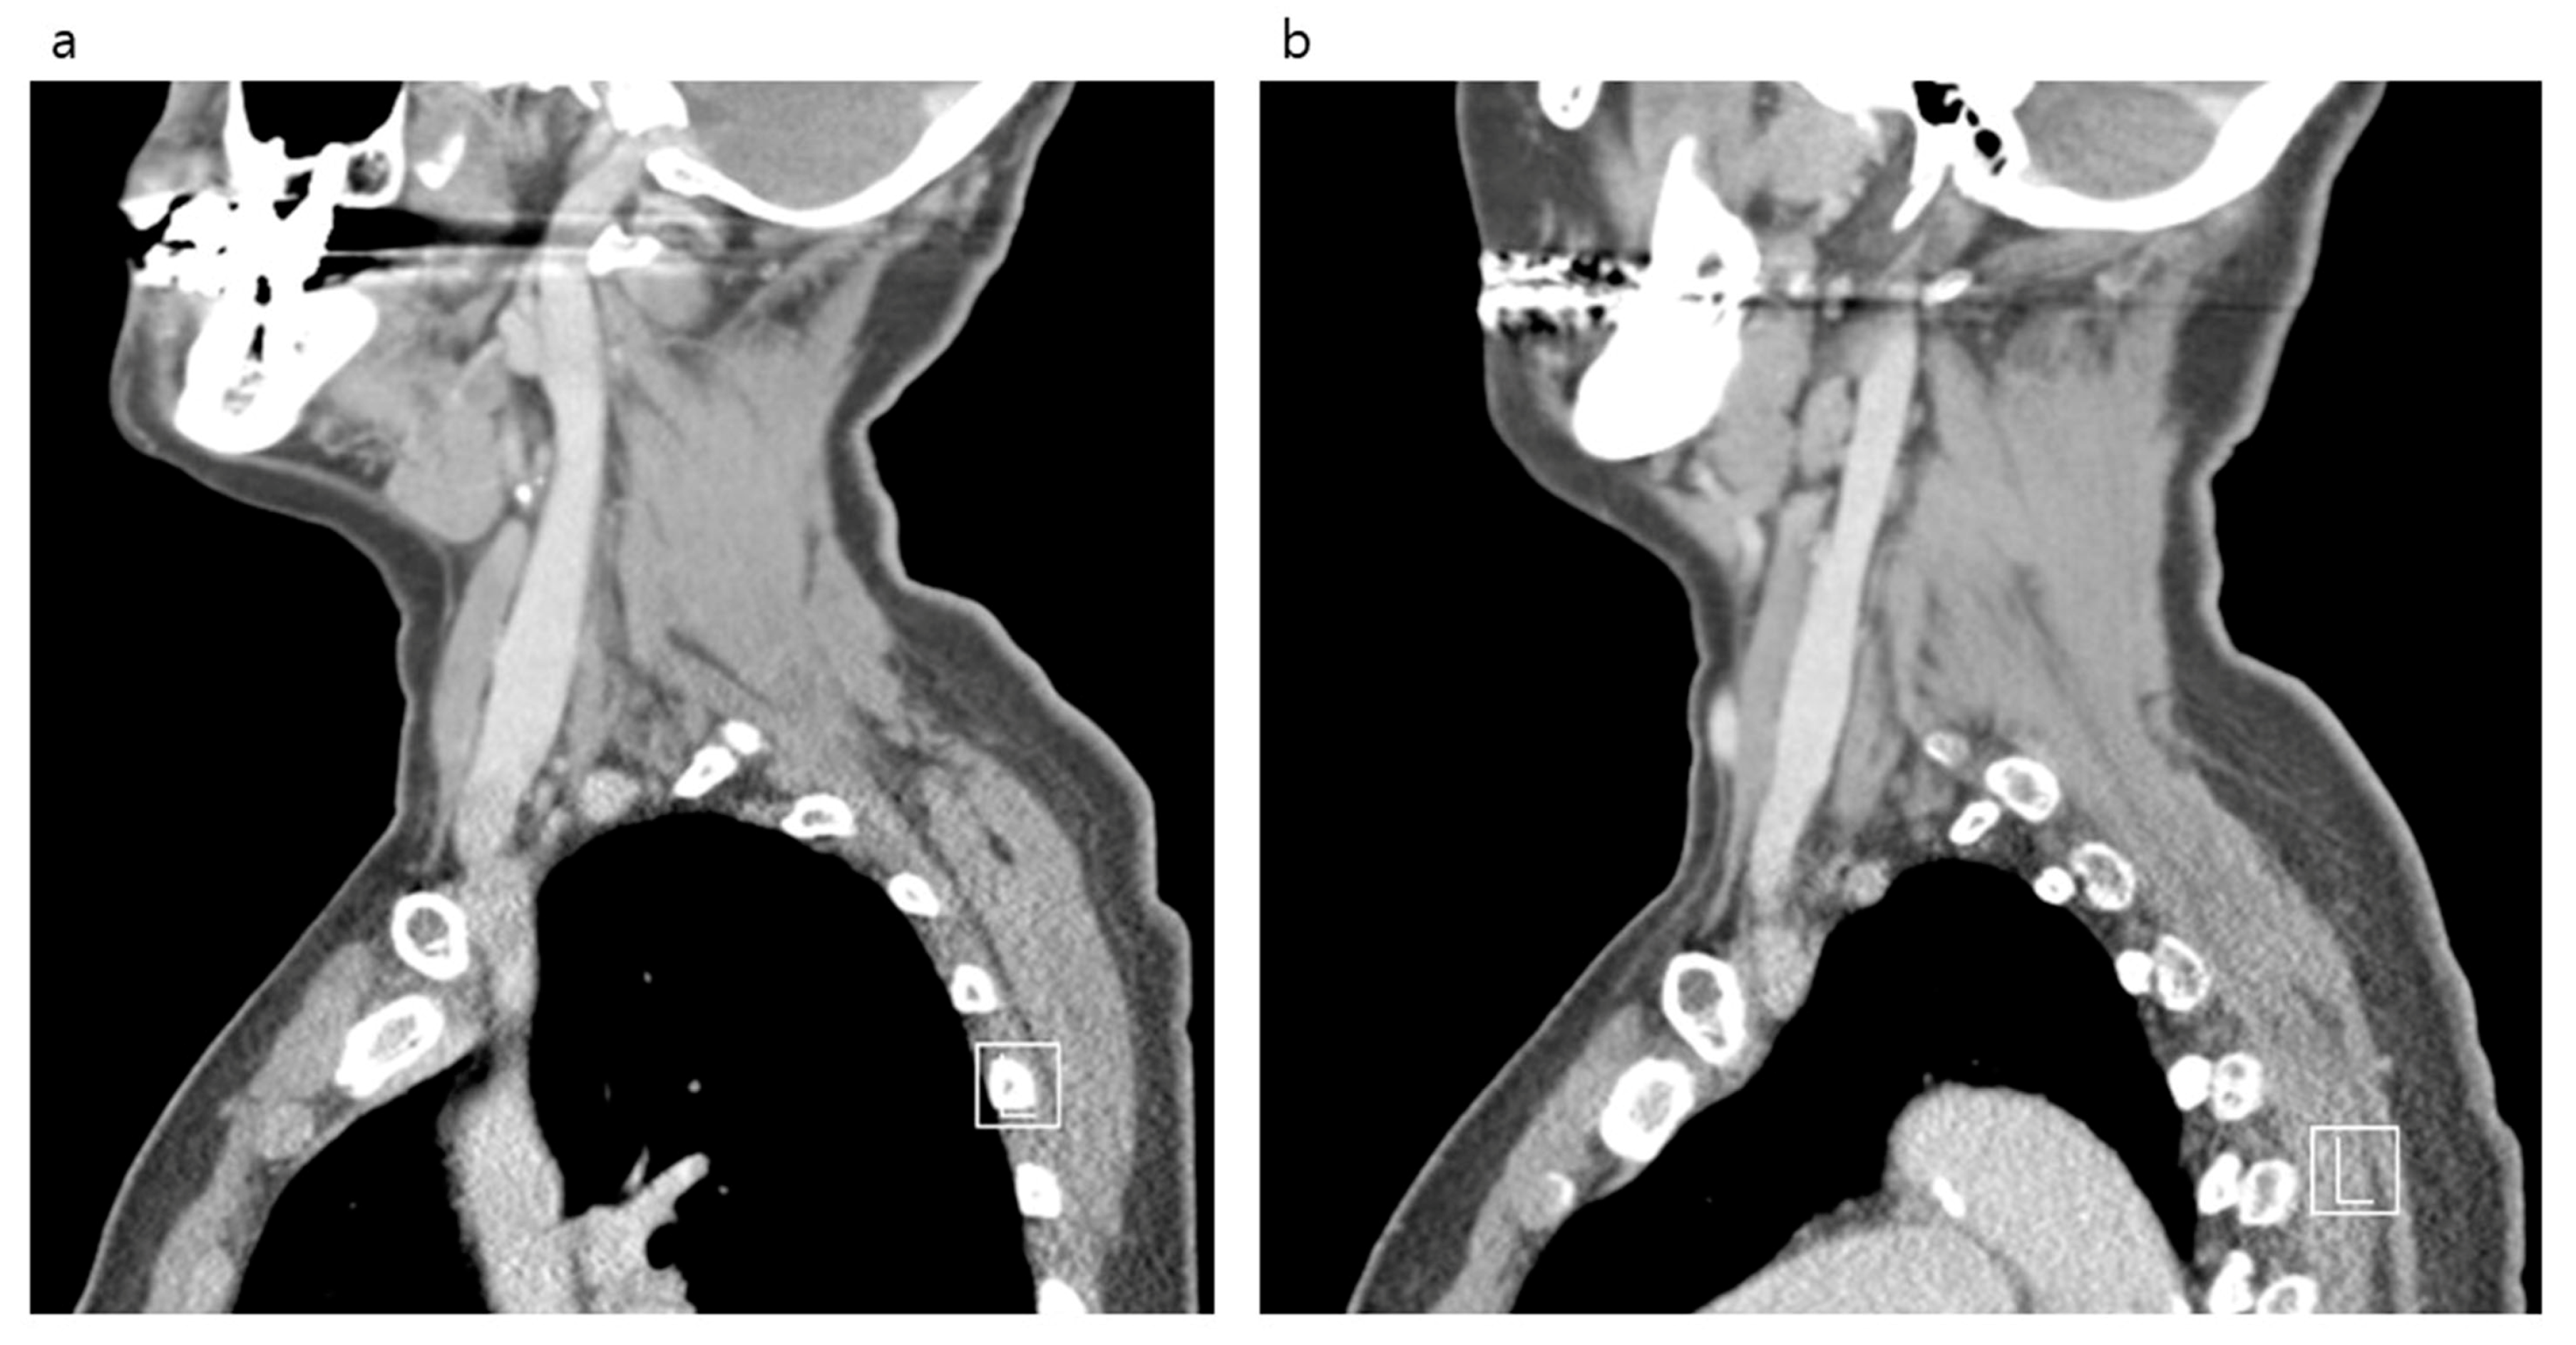

| Right | Diameter (mm) | 14.3 (12.3–16.8) | 17.6 (14.8–20.9) | 16.5 (14.2–19.1) | <0.001 |

| Area (mm2) | 124.3 (98.7–176.2) | 190.8 (137.2–258.0) | 183.1 (127.6–241.6) | <0.001 | |

| Left | Diameter (mm) | 12.0 (10.2–14.6) | 14.4 (11.8–17.5) | 11.8 (10.2–13.8) | <0.001 |

| Area (mm2) | 89.1 (65.1–124.9) | 127.0 (88.0–180.2) | 94.5 (68.7–126.7) | <0.001 |